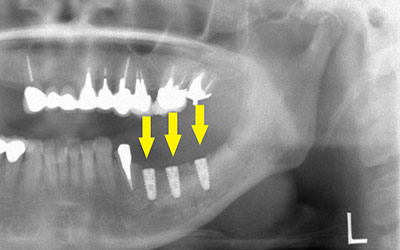

患者様の治療前のレントゲン写真です。写真の黄色矢印部の歯の周囲は、重度の歯周病で大きく歯槽骨が吸収されてしまっていました。そのため、写真の、赤色矢印で示す、下顎骨の中を通る神経までの距離がなく、インプラント埋入には、骨の高さが不足していました。

インプラント埋入後のレントゲン写真です。骨の高さが十分に確保されたので、神経を傷つけることなく、安全にインプラント埋入手術ができました。